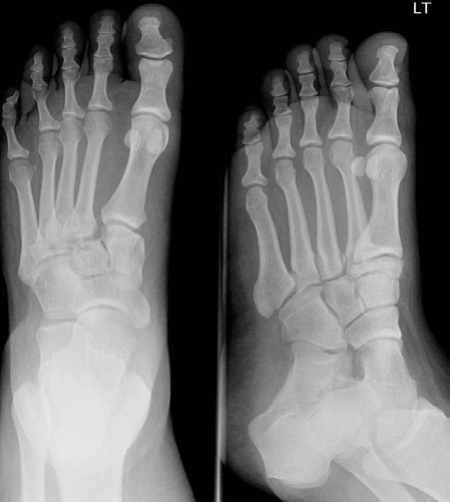

Lower limb Trauma Structured oral examination question 9 A 29-year-old female horse rider fell off her horse;…